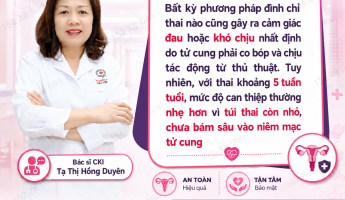

Bác sĩ Tạ Thị Hồng Duyên

BS.CKI – Bệnh viện Phụ Sản

Vì mang thai ngoài ý muốn, vẫn còn đi học, kinh tế không cho phép, không đảm bảo sức khỏe mà nhiều chị em phụ nữ lựa chọn bỏ thai khi phát hiện thai 2 tháng tuổi. Nhưng vấn đề khiến hầu hết chị em băn khoăn là “2 tháng có phá được không” hay “phá bằng cách nào”, ” phá có mang thai được nữa không”. Nội dung bài viết dưới đây, ThS.BS Sản phụ khoa Tạ Thị Hồng Duyên – Trưởng khoa Phụ Sản Đa khoa Quốc tế Hà Nội sẽ giải đáp các vấn đề liên quan tới phá thai 2 tháng tuổi.

Theo bác sĩ Tạ Thị Hồng Duyên, thai 2 tháng đã làm tổ trong buồng tử cung và kích thước thai không quá to nên có thể thực hiện đình chỉ thai. Tuy nhiên, nữ giới nên đến cơ sở y tế chuyên khoa uy tín để được thăm khám, tư vấn và đình chỉ thai an toàn.

Phá thai 2 tháng tuổi thường được bác sĩ chỉ định thực hiện bằng phương pháp hút thai – đây là phương pháp đình chỉ thai ngoại khoa bằng cách sử dụng thiết bị y tế chuyên dụng vào buồng tử cung để đưa thai nhi ra bên ngoài. Quá trình thực hiện nhanh chóng, diễn ra trong khoảng 15 – 20 phút.

Phá thai bằng hút thai mang lại hiệu quả cao, hạn chế tình trạng sót thai, sót nhau thai khi được thực hiện bởi bác sĩ giỏi.

Là phương pháp ngoại khoa do đó, hút thai cần được thực hiện trong môi trường vô khuẩn bởi đội ngũ bác sĩ có kinh nghiệm dày dặn. Điều này nhằm đảm bảo ca đình chỉ thai diễn ra an toàn, tránh các rủi ro tiềm ẩn có thể xảy ra như sót thai, sót nhau thai, thủng tử cung, băng huyết, nhiễm trùng.